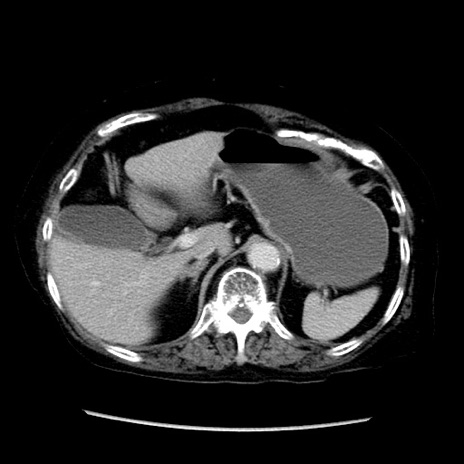

冠状断像

症例14(横断像)

【症例】 90歳代女性

【主訴】 腹痛・嘔吐

【現病歴】今朝から左側腹部痛を認めた。 経過観察していたが、嘔吐を認めたため来院。

【既往歴】 子宮癌術後

【身体所見】 意識清明、BP 127/54mmHg、P 98bpm Sp02 95%(RA)、BT 35.8°C、腹部平坦・軟腸ぜん動音聴取良好、右下腹部圧痛(+) 反跳痛なし

【データ】WBC 9800、CRP 0.46